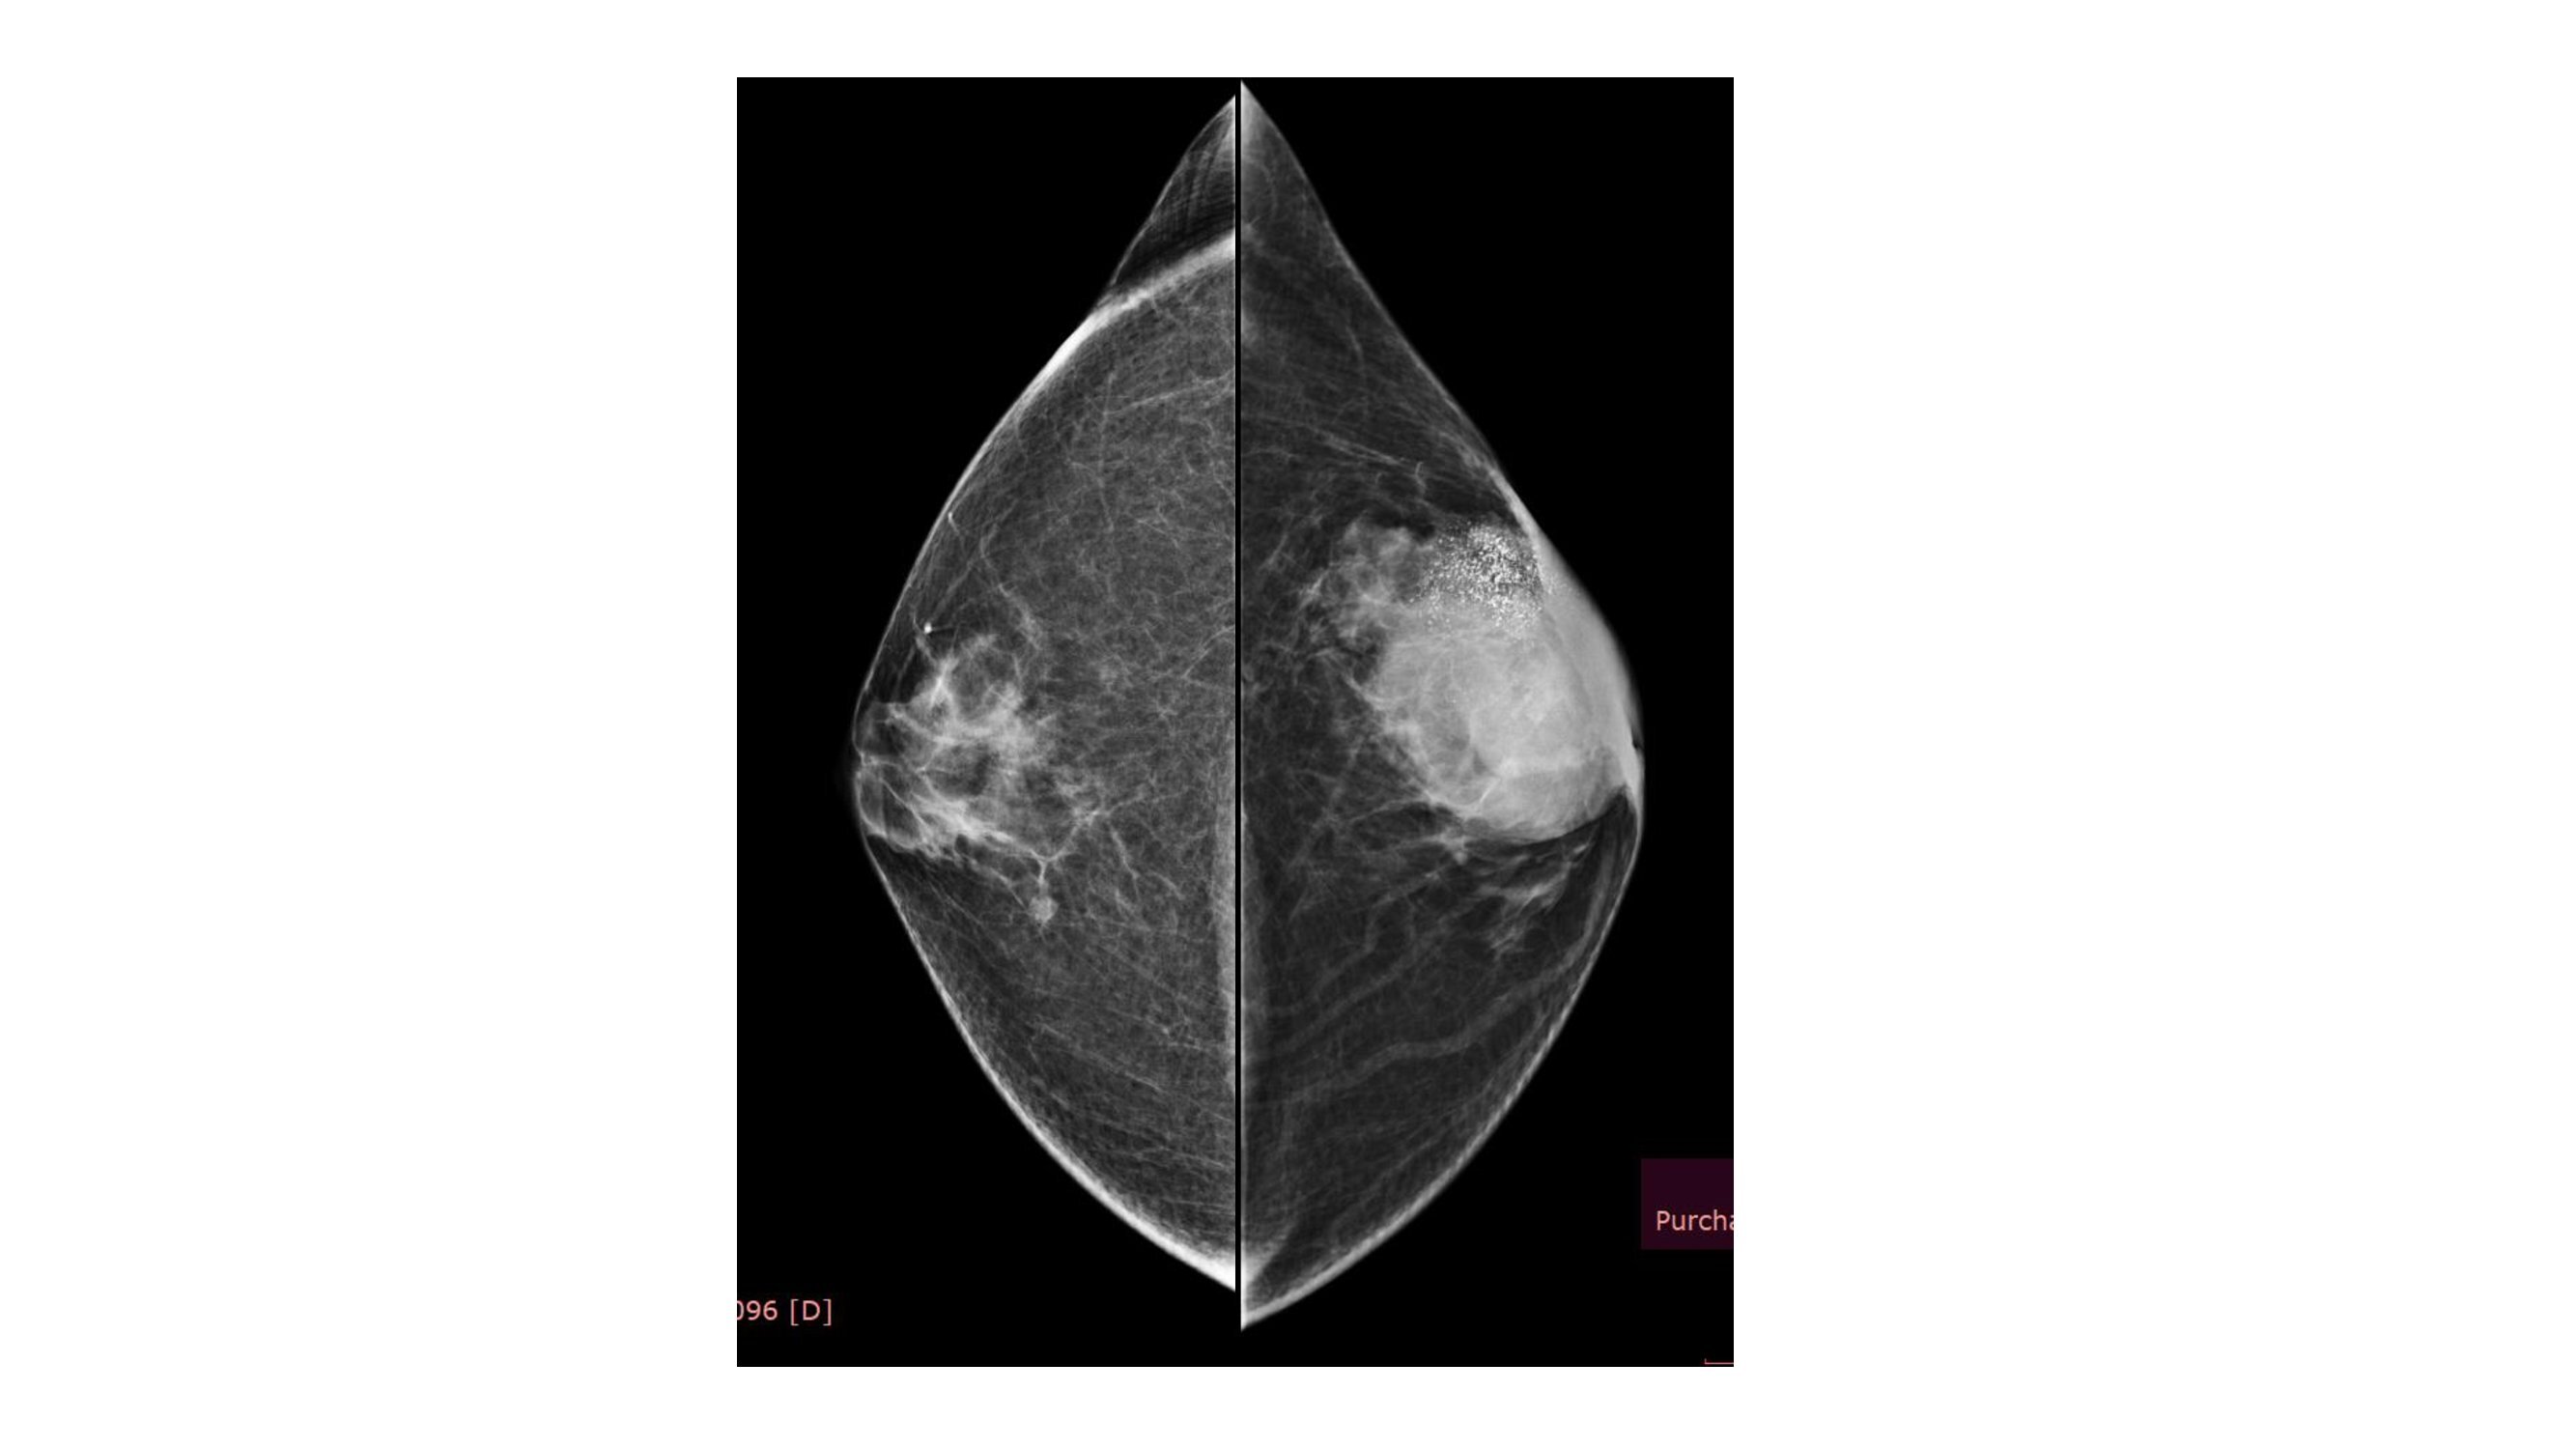

A 55 years old female came for screening mammogram....

Read More